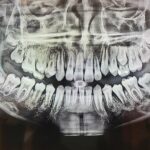

일반적으로 충치로 알려진 충치 레진은 치료하지 않고 방치하면 치아에 심각한 손상을 일으킬 수 있습니다. 이 글에서는 충치 레진의 원인, 증상, 치료 방법 및 예방법에 대해 알아보겠습니다.

충치 레진은 치아의 구부러진 부분에 박테리아와 충치가 침투할 때 발생하는 질환입니다. 시간이 지남에 따라 치아의 에나멜 층에 충치 레진이 형성됩니다.

충치 레진은 통증 및 발치 필요성과 같은 증상을 유발할 수 있습니다. 치료하지 않고 방치하면 순환계와 호흡기에도 부정적인 영향을 미칠 수 있습니다. 일반적으로 충치 레진은 철, 인, 칼슘, 탄산염 및 박테리아로 구성된 치아에 검은색 또는 갈색 반점으로 나타납니다.

치료를 시작하기 전에 치아 전체에 대한 종합적인 검사가 필요합니다. 적절한 치료 방법을 선택하고 엄격하게 따르는 것이 중요합니다. 치료 후 원하는 결과를 얻으려면 치아를주의 깊게 관리하는 것이 중요합니다.